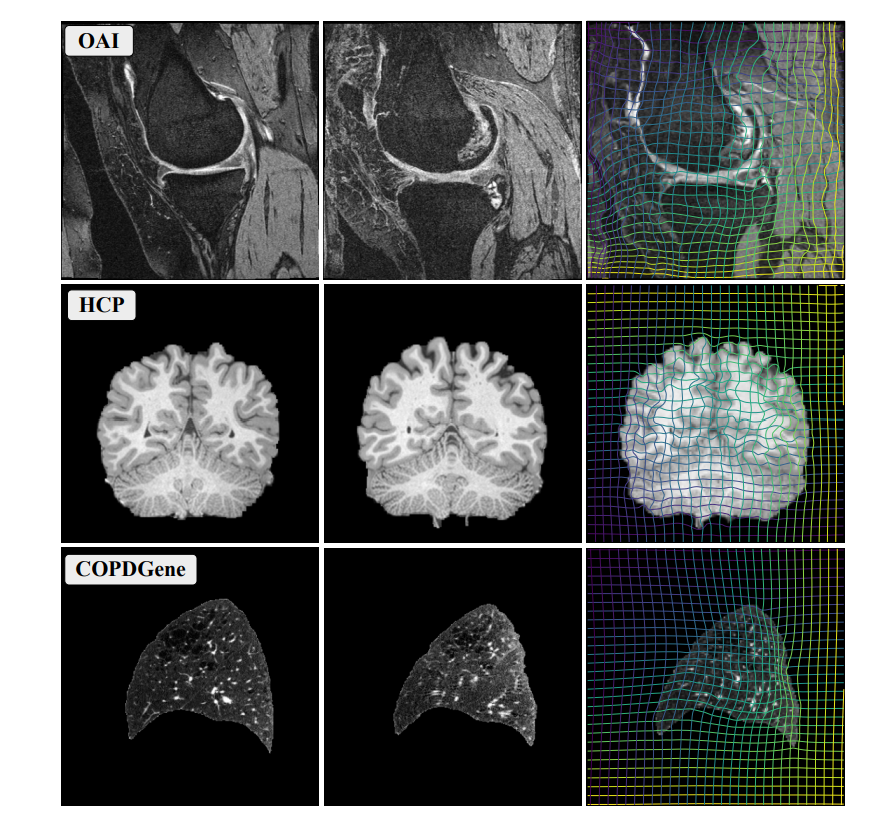

5. ECCV

NePhi_teaser.png

NePhi: Neural Deformation Fields for Approximately Diffeomorphic Medical Image Registration

Lin Tian, Hastings Greer, Raúl San José Estépar, and 2 more authors

arXiv preprint arXiv:2309.07322, 2024

ECCV 2024